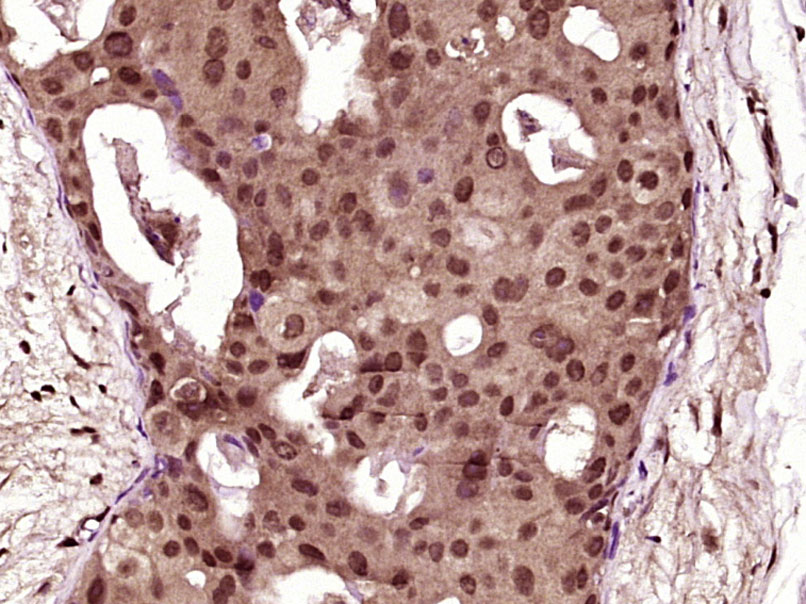

Paraformaldehyde-fixed, paraffin embedded (Human breast carcinoma); Antigen retrieval by boiling in sodium citrate buffer (pH6.0) for 15min; Block endogenous peroxidase by 3% hydrogen peroxide for 20 minutes; Blocking buffer (normal goat serum) at 37°C for 30min; Antibody incubation with (RRAS) Polyclonal Antibody, Unconjugated (bs-7574R) at 1:400 overnight at 4°C, followed by operating according to SP Kit(Rabbit) (sp-0023) instructionsand DAB staining.